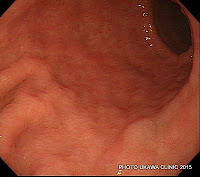

カンピロバクター腸炎はPI-IBSの原因として最も知られており、腸炎後のギランバレー症候群もとても嫌で、かかって欲しくない病気だ。焼肉は火を通すだけではなく、肉を触った箸にも注意を払ってほしいと本当に思う。以前は牛の生レバー、現在は鶏肉での感染が多い。アメリカはバーベキューを良くするせいなのか、汚染された鶏肉が多いのか、両方なのか、わからないけれどこの食中毒がとても多いので研究が進んでいる。上行結腸に強い炎症が生じるのが特徴で、強い腹痛を訴え、「火を通した」と言っても鶏肉を食べていたらエコーを行ってみると著明に腫れているので予測がつけられることが多い。便培養では検出できず、大腸内視鏡で回盲部の組織をとって培養したところ診断がついたこともある。class A lipo-oligosaccharide(LOS)遺伝子を持つカンピロバクターは、腸炎後のギランバレー症候群や関節炎、PI-IBSの発症に関連するかもしれず、今後の研究が待たれる。